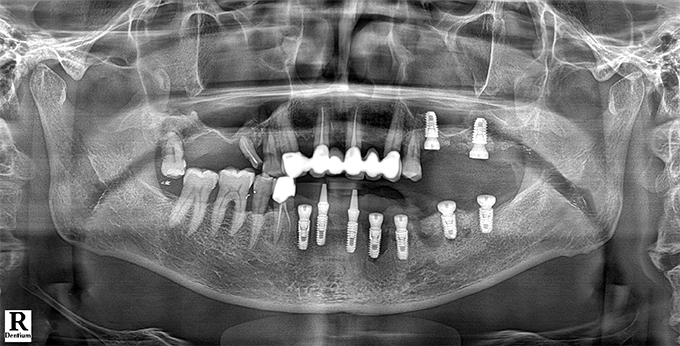

Before & After

임플란트 전후사진

before

2022.10.24

After

2022.11.01

※ 상기 치료전후 사진은 환자의 동의 하에 게재되는 것이며 동일한 촬영각도로 촬영 하였고 치료 기간을 명시하였습니다.

이러한 치료의 결과는 이 환자분에게만 해당되는 것이며 환자의 상태에 따라 똑같은 결과를 얻지 못할 수도 있습니다.

환자분의 상태에 따라 치료 기간, 효과 및 부작용은 상이할 수 있습니다.

치료전후 사진 게재는 의료법 제 23조, 제56조에 의거하여 게재합니다.